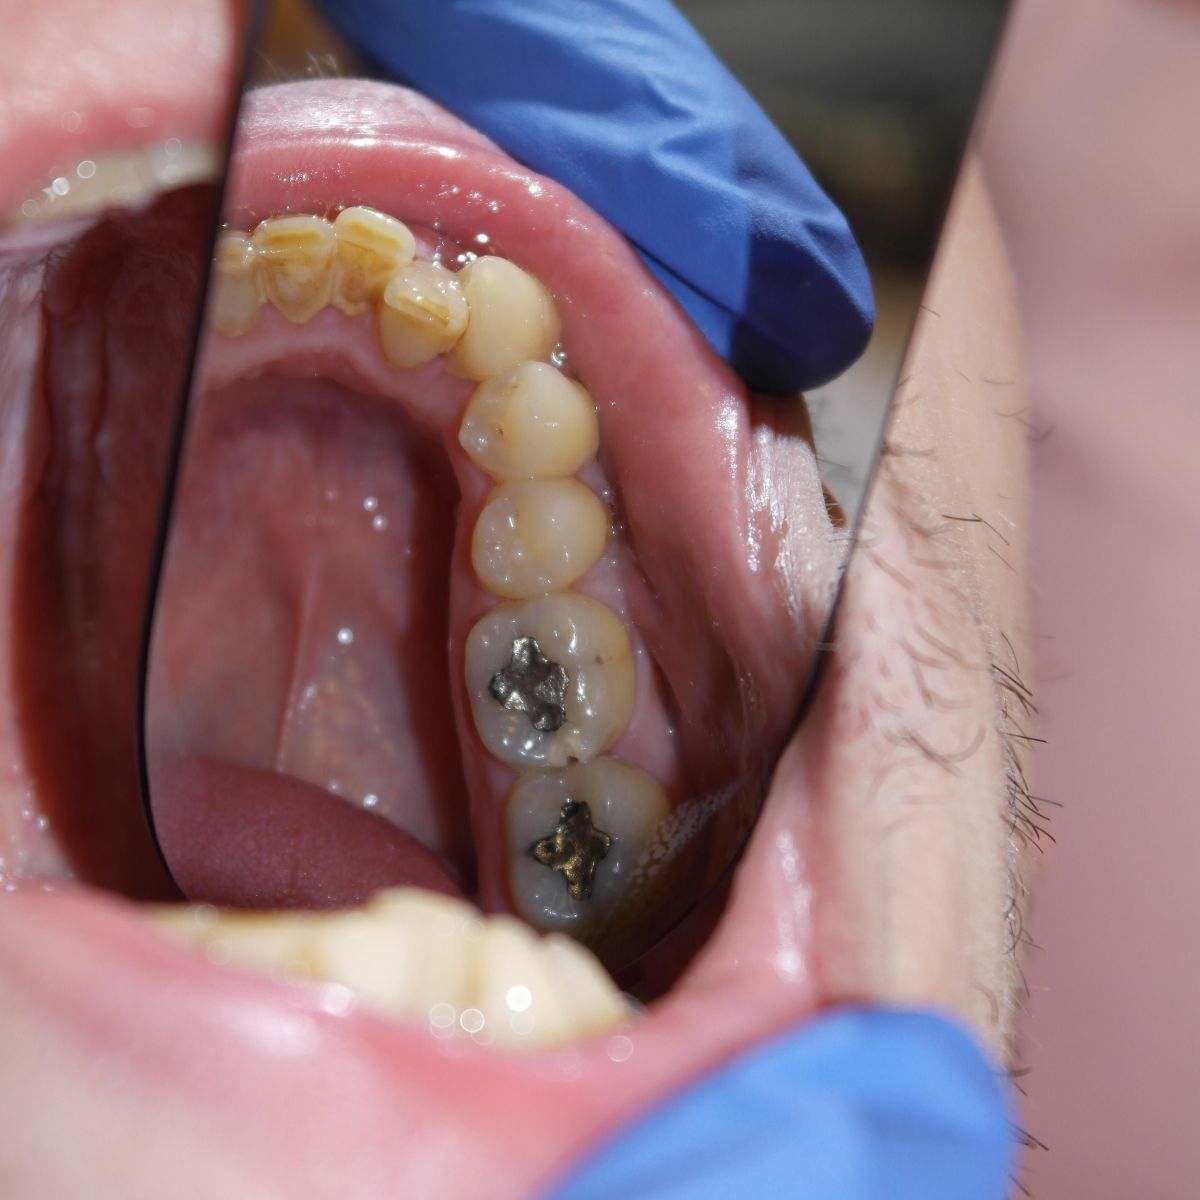

A fogászatban tömés alatt azt a műveletet értjük, mely során különböző anyagok fogba helyezésével helyreállítjuk a sérült fog egységét. A fog tömése fúrással kezdődik, amikor is a fogorvos feltárja a szuvas részeket, és megtisztítja az érintett részeket. Az így keletkezett lyukat tölti ki a fogtömő anyaggal.

Töméskor tehát a szuvas részt mindenképpen el kell távolítani, ezután tömhető be a lyuk, amelyre többféle anyag is használható:

Kisméretű kerámia szemcsék segítségével erősített kompozitból áll, melyek a természetes fogak színével megegyeznek és jó a kopásállóságuk. Legtöbbször fogszuvasodás miatt károsodott fogaknál vagy amalgám tömés eltávolítását követően használjuk. Élettartama általában 10 év.